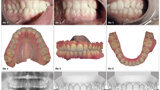

Malokluze I. třídy léčená pomocí F22 Aligners